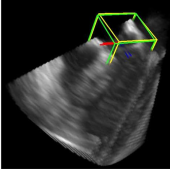

利用2891次心脏超声检查的数据集,Ghesu等结合深度学习和边缘空间学习进行医学图像检测和分割[12]。“大参数空间的有效探索”和在深度网络中实施稀疏性的方法相结合,提高了计算效率,并且与同一组发布的参考方法相比,平均分割误差减少了13.5%,八位患者的检测结果如图4所示。Brosch等人利用MRI图像上研究多发性硬化脑病变分割的问题。开发了一种3D深度卷积编码器网络,它结合了卷积和反卷积[13],图5.增加网络深度对病变的分割性能的影响。卷积网络学习了更高级别的特征,并且反卷积网络预进行像素级别分割。将网络应用于两个公开的数据集和一个临床试验数据集,与5种公开方法进行了比较,展现了最好的方法。Pereira等人的研究中对MRI上的脑肿瘤分割进行了研究,使用更深层的架构,数据归一化和数据增强技巧[14]。将不同的CNN架构用于肿瘤,该方法分别对疑似肿瘤的图像增强和核心区域进行分割。在2013年的公共挑战数据集上获得了最高成绩。

图5.增加网络深度对病变的分割性能的影响。真阳性,假阴性和假阳性体素分别以绿色,黄色和红色突出显示。由于感受野的大小增加,具有和不具有捷径的7层CEN能够比3层CEN更好地分割大的病变。